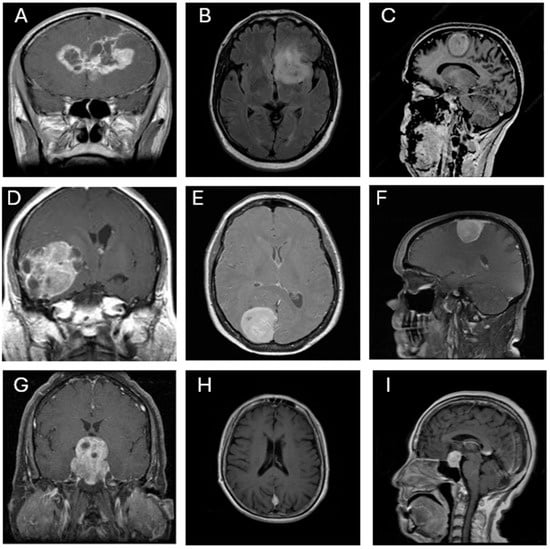

This study utilized the publicly available Brain Tumor Classification dataset sourced from Kaggle (https://www.kaggle.com/datasets/prathamgrover/brain-tumor-classification, obtained at 5 November 2024) for training and building the CNN models. The primary dataset consists of 3261 contrast-enhanced T1-weighted MRI images classified into four categories: glioblastoma (926 images), meningioma (934 images), pituitary adenoma (901 images), and no tumor (500 images). For external testing and generalizability assessment, a second open-source dataset was employed (https://www.kaggle.com/datasets/rm1000/brain-tumor-mri-scans, obtained at 4 July 2025). This dataset comprises 7023 contrast-enhanced T1-weighted MRI images, also classified into four categories: glioblastoma (1261 images), meningioma (1645 images), pituitary adenoma (1757 images), and no tumor (2000 images). All images are grayscale and were pre-annotated based on confirmed clinical/surgical diagnoses. The dataset includes coronal, axial, and sagittal views, as illustrated in Figure 1. Each image was resized to 300 × 300 pixels and normalized to ensure consistent input across all CNN architectures.

Figure 1.

Representative MRI images of three types of brain tumors. (A,B,D) Glioblastoma, (C,E,F,H) meningioma, and (G,I) pituitary adenoma, shown in various orientations (coronal, axial, and sagittal views).